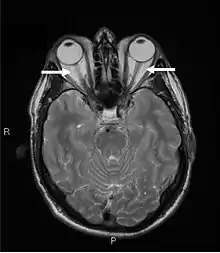

Orbital imaging is an integral tool for the diagnosis of Graves' ophthalmopathy and is useful in monitoring patients for progression of the disease. It is, however, not warranted when the diagnosis can be established clinically. Ultrasonography may detect early Graves' orbitopathy in patients without clinical orbital findings. It is less reliable than the CT scan and magnetic resonance imaging (MRI), however, to assess the extraocular muscle involvement at the orbital apex, which may lead to blindness. Thus, CT scan or MRI is necessary when optic nerve involvement is suspected. On neuroimaging, the most characteristic findings are thick extraocular muscles with tendon sparing, usually bilateral, and proptosis.